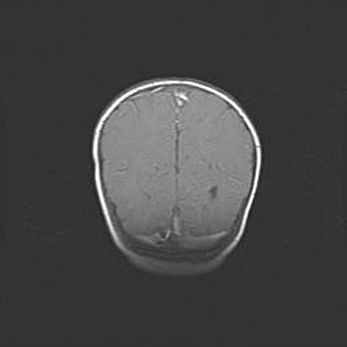

Церебральная ишемия II.

Возраст: 5 дней

Вес: 3400 г

Пол: женский

Окружность головы: 35 см

Срок гестации: 39 недель

Церебральная ишемия – это заболевание, характеризующееся недостаточностью (гипоксией) либо полным прекращением (аноксией) снабжения мозга кислородом по причине закупорки одного или нескольких сосудов. Это приводит к  что метаболическим расстройствам различной степени тяжести в тканях головного мозга, развитию коагуляционных некрозов и гибели нейронов.